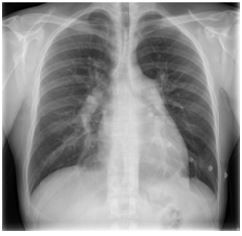

Homem, 42 anos, refere dispneia aos esforços há cinco meses, com sensação de opressão no tórax há uma semana. Nega tosse, expectoração ou chiado. Nega tabagismo. Exame físico: PS 120/79 mmHg; FC 86 bpm; saturação de O2 (ar ambiente) 91%. Ausculta cardíaca: hierfonese e desdobramento de segunda bulha em foco pulmonar. Turgência jugular bilateral. Pulmões limpo. Exames laboratoriais: hemoglobina 12,2 g/dL; leucocitos 8.500/mm³ plaquetas 152.000/mm³. Radiograma de toráx:

O exame indicado para iniciar a investigação da dispneia desta paciente é: